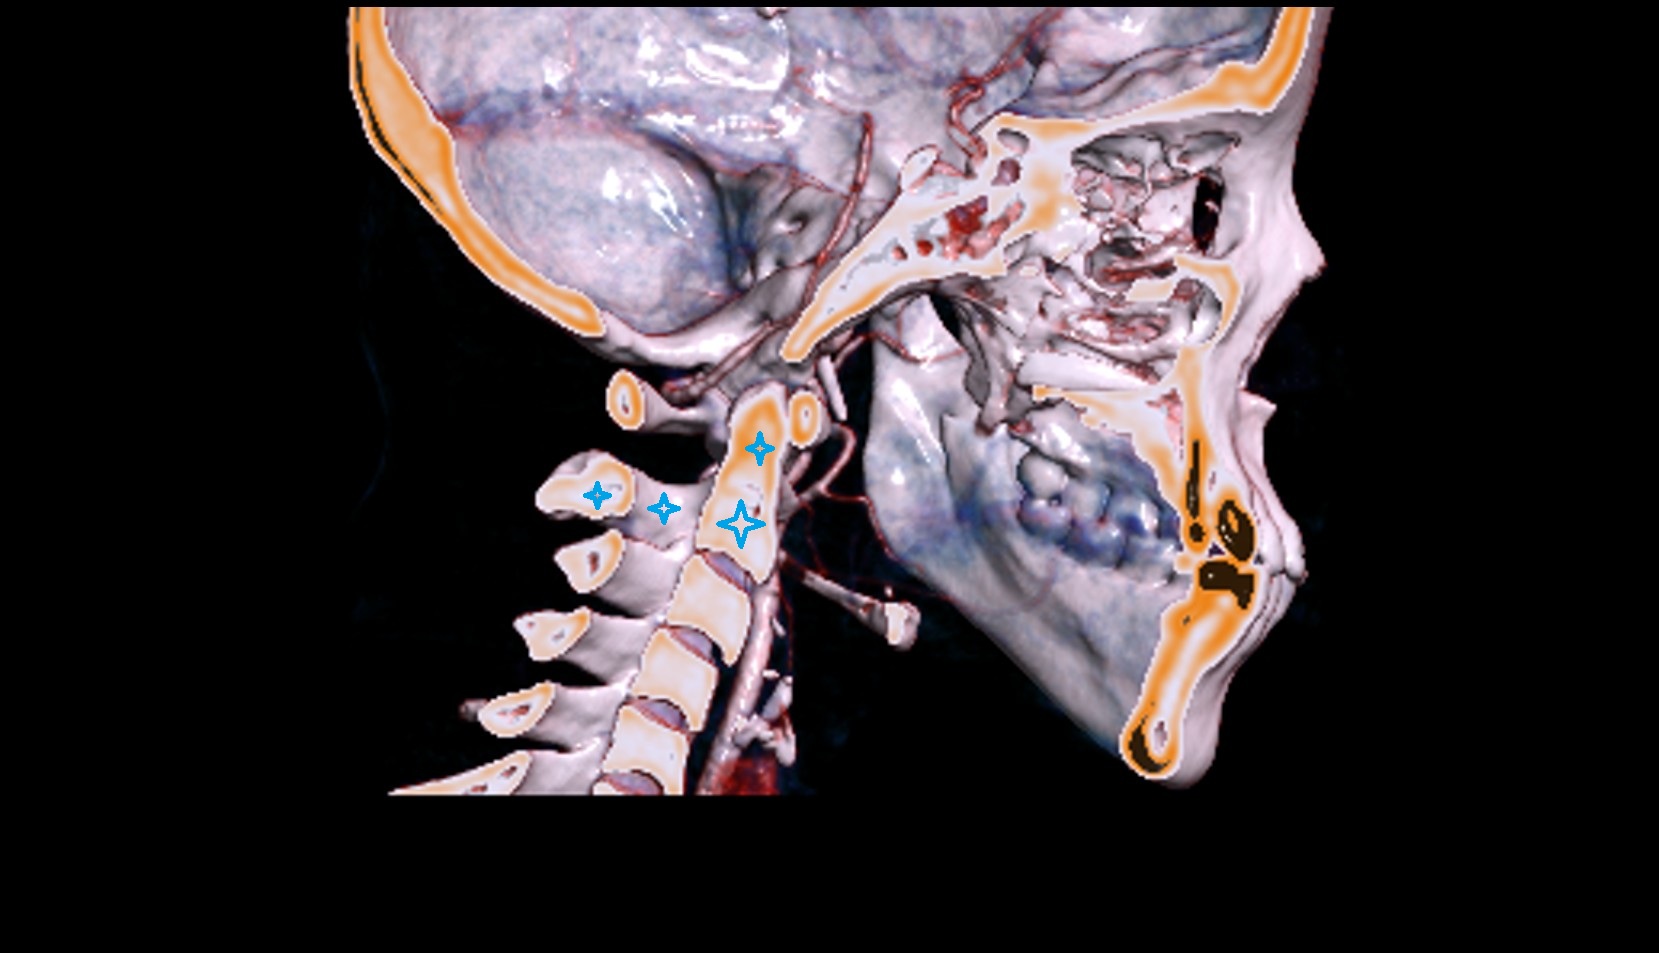

- Axis (C2 vertebra)

- Atlantooccipital joint

- Lateral atlantoaxial joint